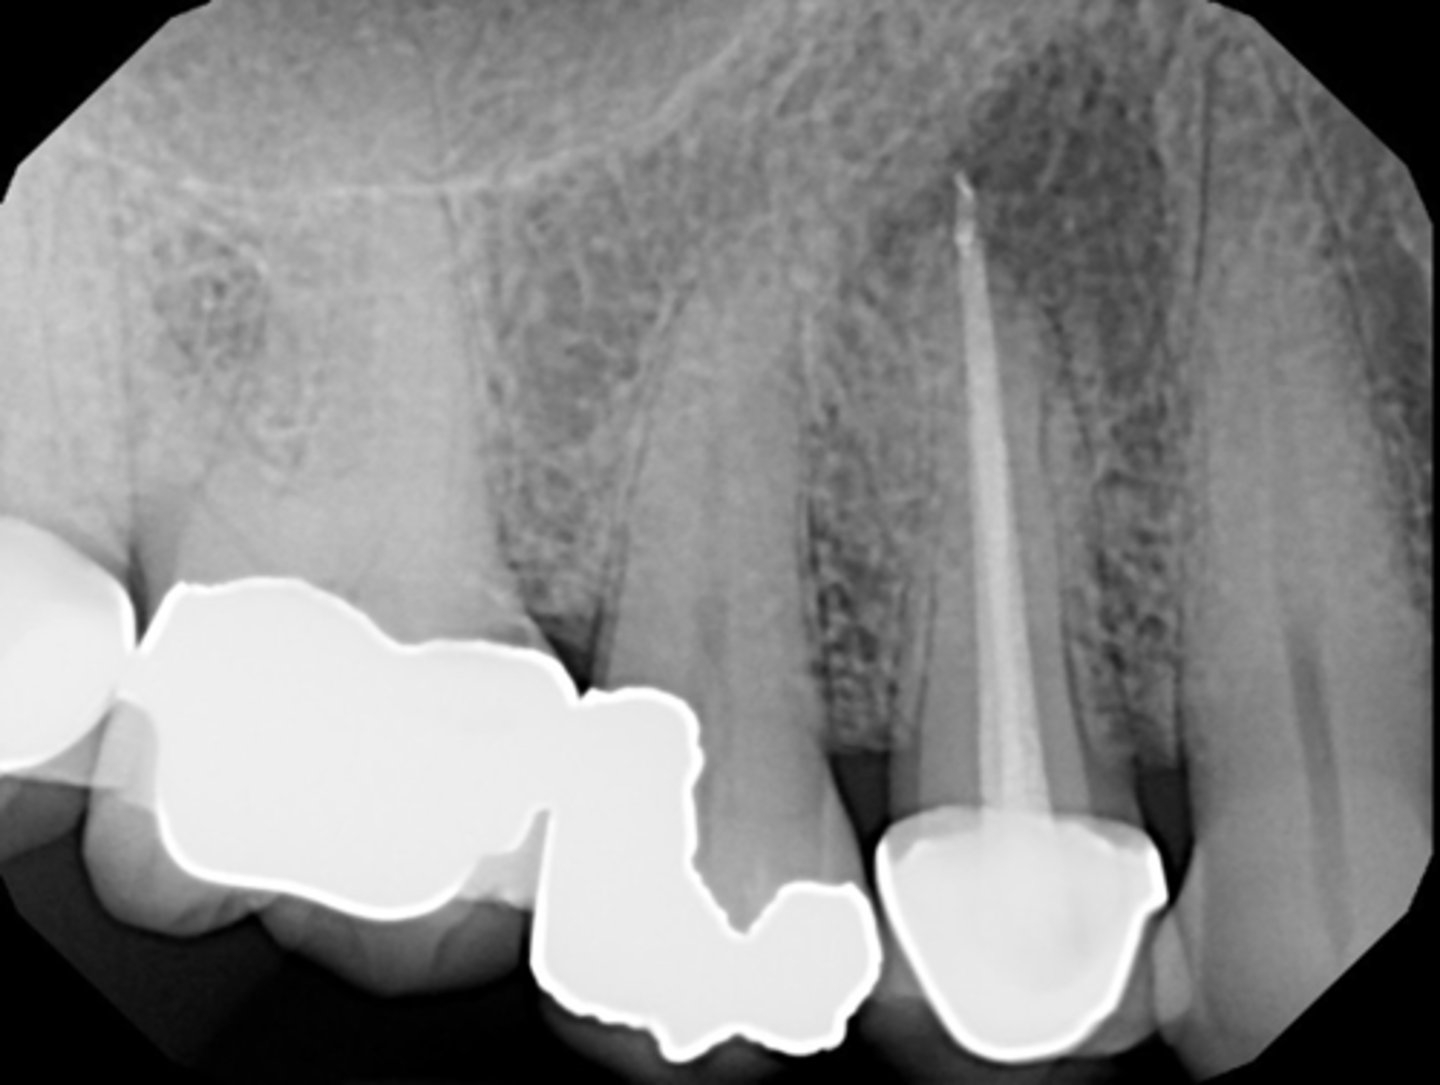

What anatomical structure is interfering with the ability to do surgery?

Mental foramen